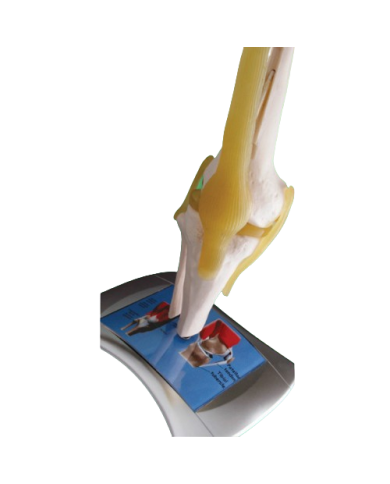

Modello anatomico PER FORNITURE CASE FARMACEUTICHE

Modello anatomico PER FORNITURE CASE FARMACEUTICHE

Modello anatomico PER FORNITURE CASE FARMACEUTICHE

Modello anatomico PER FORNITURE CASE FARMACEUTICHE

Modello anatomico PER FORNITURE CASE FARMACEUTICHE

Modello anatomico PER FORNITURE CASE FARMACEUTICHE

Modello anatomico PER FORNITURE CASE FARMACEUTICHE

Modello anatomico PER FORNITURE CASE FARMACEUTICHE

Modello anatomico PER FORNITURE CASE FARMACEUTICHE

Modello anatomico PER FORNITURE CASE FARMACEUTICHE

Modello anatomico PER FORNITURE CASE FARMACEUTICHE

Modello anatomico PER FORNITURE CASE FARMACEUTICHE

Modello anatomico PER FORNITURE CASE FARMACEUTICHE

Modello anatomico PER FORNITURE CASE FARMACEUTICHE

Modello anatomico PER FORNITURE CASE FARMACEUTICHE

Modello anatomico PER FORNITURE CASE FARMACEUTICHE

Modello anatomico PER FORNITURE CASE FARMACEUTICHE

Modello anatomico PER FORNITURE CASE FARMACEUTICHE

Modello anatomico PER FORNITURE CASE FARMACEUTICHE

Modello anatomico PER FORNITURE CASE FARMACEUTICHE

Modello anatomico PER FORNITURE CASE FARMACEUTICHE

Modello anatomico PER FORNITURE CASE FARMACEUTICHE